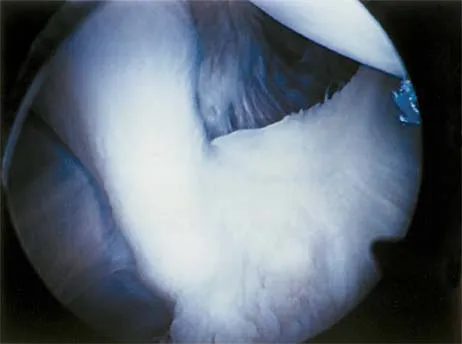

A patient undergoes hip arthroscopy, and the pathology is seen in Figure 18. What is the most likely diagnosis?